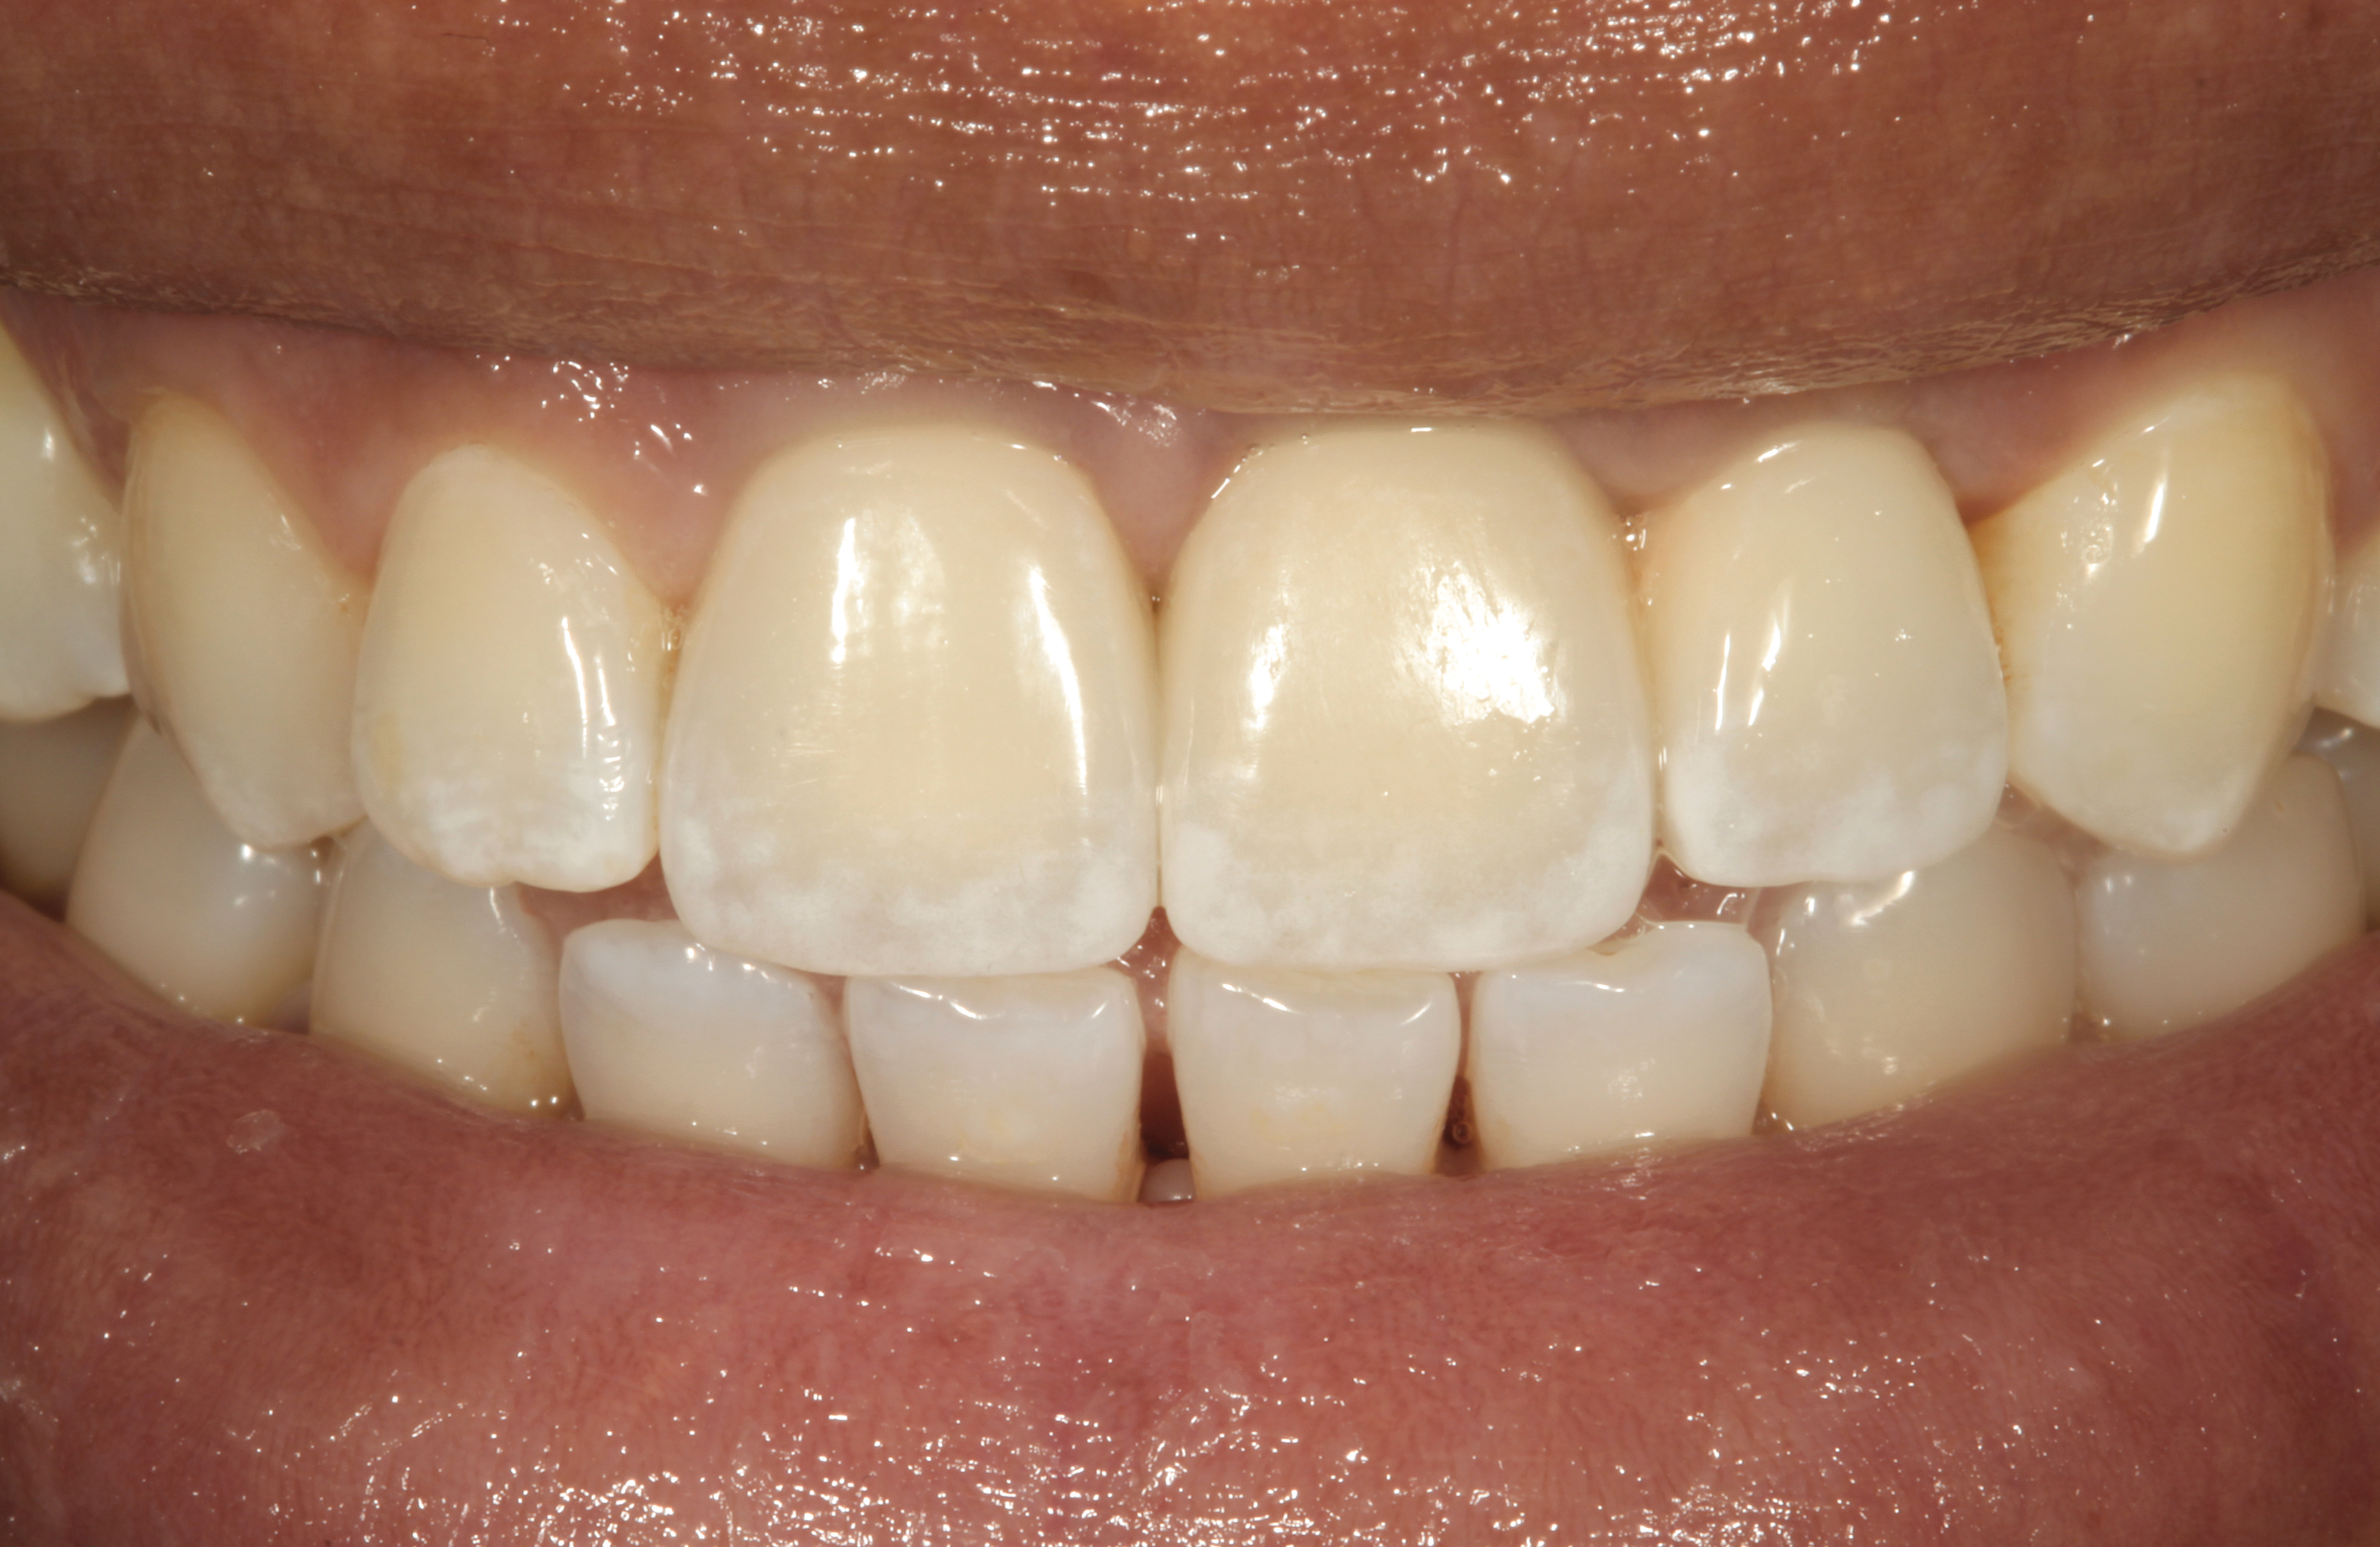

Fig 1. Midfacial recession can affect the esthetics of a smile and lead to an unsatisfactory outcome.

Fig 2. The cause for midfacial recession is excessive labial implant placement. Secondary to poor placement is overcontouring of the implant abutment.

Fig 3. A patient presented with a high smile line and midfacial recession of the maxillary right lateral incisor as evidenced by the increased tooth length compared with the contralateral lateral incisor.

Figure 3

Fig 4. Intraoral view of tooth No. 7 with the gingival zenith more apical than the adjacent central incisor and canine tooth.